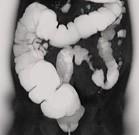

问题 女,56岁,腹胀、腹痛、左下腹包块三月余,无肛门排气,影像检查如图,最可能的诊断是()

选项 A.乙状结肠Crohn病 B.乙状结肠结核 C.乙状结肠腺癌 D.乙状结肠淋巴瘤 E.乙状结肠息肉

答案 C